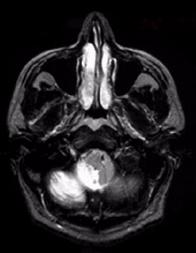

• Testing the fifth cranial nerve in a patient with seventh nerve palsy (acoustic neuroma)